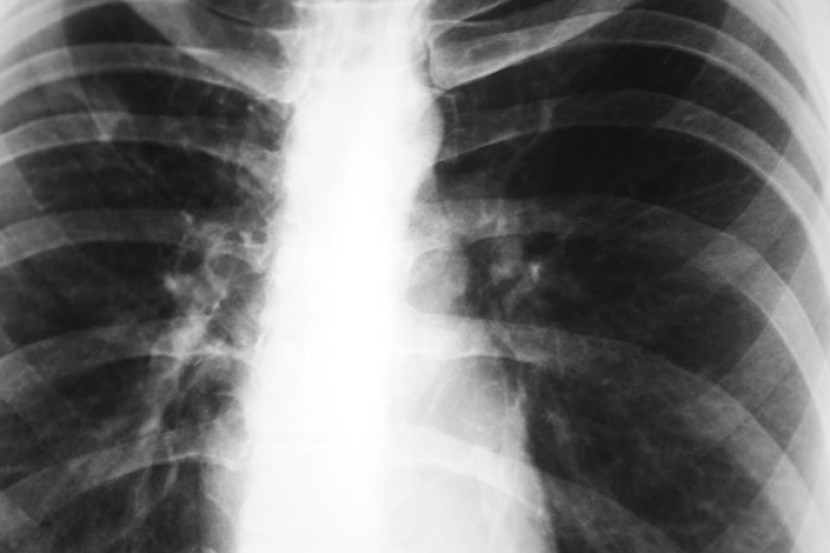

KUALA LUMPUR: Kira-kira 24,000 kes penyakit tuberkulosis (tibi) atau batuk kering telah dilaporkan di negara ini tahun lepas dan ia berada ditahap membimbangkan, kata Menteri Kesihatan Datuk Seri Dr S. Subramaniam.

Beliau berkata berdasarkan laporan bagi penyakit berjangkit tibi pada 2013 menunjukkan penurunan jumlah kes tetapi meningkat kembali pada tahun lepas, sebanyak enam peratus.

"Ini memang satu perkara yang tidak memuaskan kerana kita masih nampak trend peningkatan kes tibi sejak kebelakangan ini.

"Terdapat pelbagai punca penyakit tibi, salah satu daripada punca penyakit adalah disebabkan ketahanan kuman-kuman terhadap rawatan kimoterapi dan pelbagai jenis ubat yang mengundang kepada peningkatan penyakit," katanya kepada pemberita selepas perasmian Kongres Pertubuhan Respiratori Asia Pasifik Ke-20 2015 (APSR 2015) di sini, Khamis.